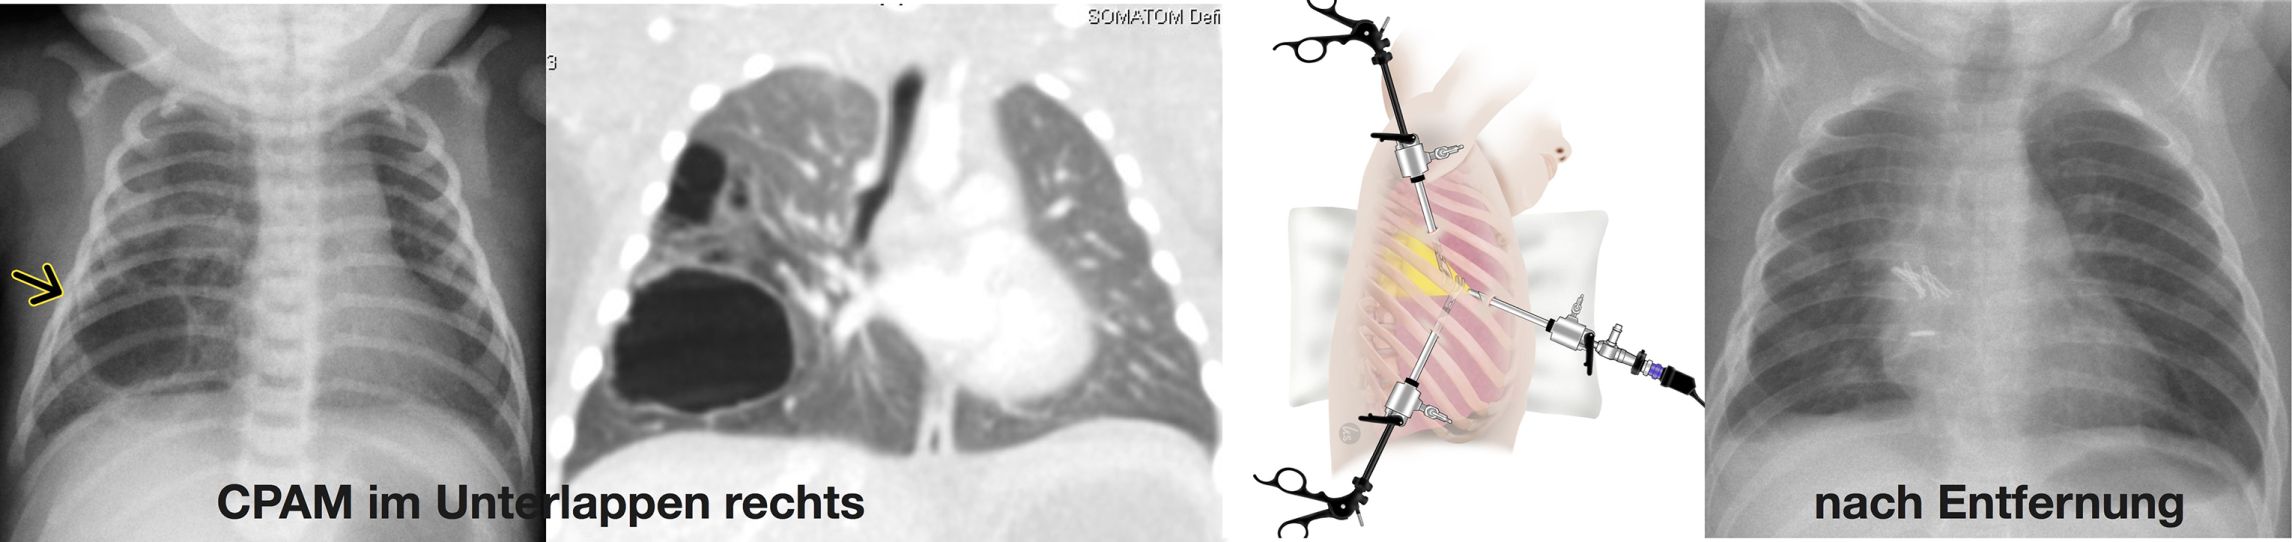

• CPAM (Congential Pulmonary Airway Malformation) früher als Zystische Malformation der Lunge (CPAM) bezeichnet: Hier handelt es sich um eine zunächst gutartige Veränderung eines Teils der Lunge, durch fehlerhafte Entwicklung in der Embryonalzeit. Der betroffene Lungenabschnitt weist teilweise solide und vor allem zystische Veränderungen des Lungengewebes auf (Abbildung).

Lungenchirurgie: Abb. links: CPAM im Unterlappen rechts. Abb. rechts: nach Entfernung

Lungenchirurgie: Linke Seite der Abbildung: CPAM im Unterlappen rechts. Rechte Seite der Abbildung: nach Entfernung.